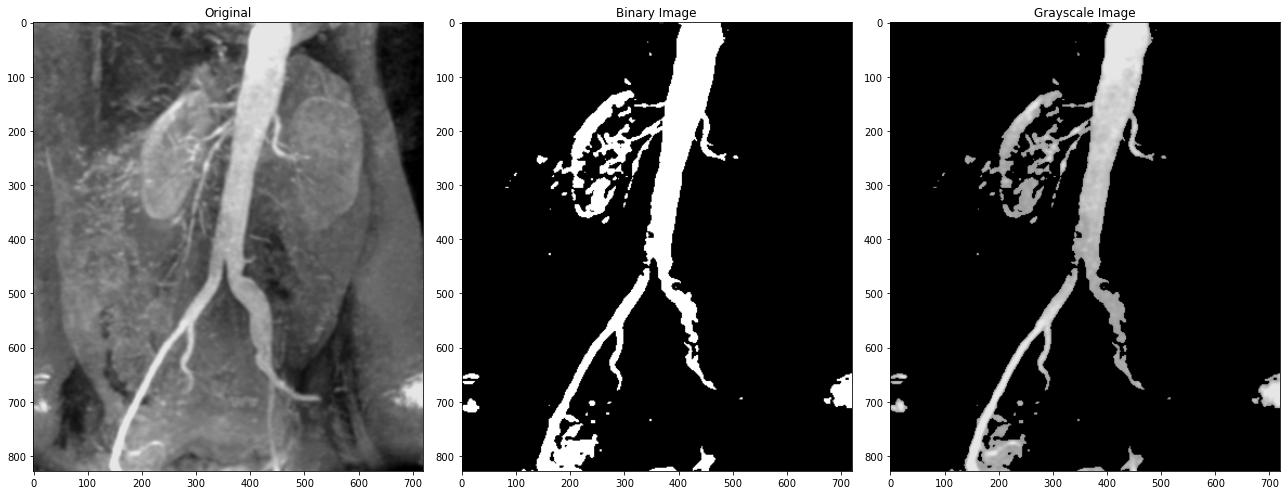

灰度级分层

-  二值图像

-  将感兴趣范围内的所有灰显示为一个值(白色),而将其它灰度值显示为另一个值(黑色)

-  其他灰度级不变

-  使期望的灰度范围变量(或变暗),但保持图像中的其它灰度级不变

img = cv2.imread('DIP_Figures/DIP3E_Original_Images_CH03/Fig0312(a)(kidney).tif')a = 155# binary image

img_transform = img.copy()

img_transform[img_transform < a] = 0

img_transform[img_transform >= a] = 255# grayscale image

img_transform_2 = img.copy()

img_transform_2[img_transform_2 < a] = 0.plt.figure(figsize=(18, 15))

plt.subplot(1, 3, 1), plt.imshow(img, cmap='gray'), plt.title('Original')

plt.subplot(1, 3, 2), plt.imshow(img_transform, cmap='gray'), plt.title(f'Binary Image')

plt.subplot(1, 3, 3), plt.imshow(img_transform_2, cmap='gray'), plt.title(f'Grayscale Image')